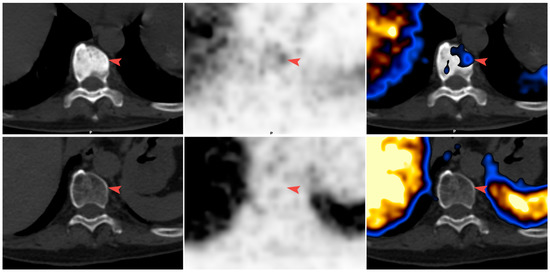

68Ga-PSMA-11 PET/CT Follow-Up of Patients with Prostate Cancer with Bone Metastases Who Had Reduced Bone Density after Androgen Deprivation Therapy

2.2. Positron Emission Tomography/Computed Tomography (PET/CT) Imaging

2.3. Image Analysis